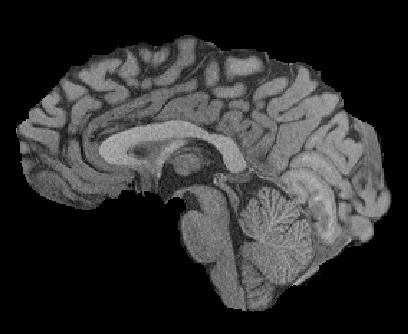

Magnetic resonance (MR) images are often acquired in 2D settings for real clinical applications. The 3D volumes reconstructed by stacking multiple 2D slices have large inter-slice spacing, resulting in lower inter-slice resolution than intra-slice resolution. Super-resolution is a powerful tool to reduce the inter-slice spacing of 3D images to facilitate subsequent visualization and computation tasks. However, most existing works train the super-resolution network at a fixed ratio, which is inconvenient in clinical scenes due to the heterogeneous parameters in MR scanning. In this paper, we propose a single super-resolution network to reduce the inter-slice spacing of MR images at an arbitrarily adjustable ratio. Specifically, we view the input image as a continuous implicit function of coordinates. The intermediate slices of different spacing ratios could be constructed according to the implicit representation up-sampled in the continuous domain. We particularly propose a novel local-aware spatial attention mechanism and long-range residual learning to boost the quality of the output image. The experimental results demonstrate the superiority of our proposed method, even compared to the models trained at a fixed ratio.